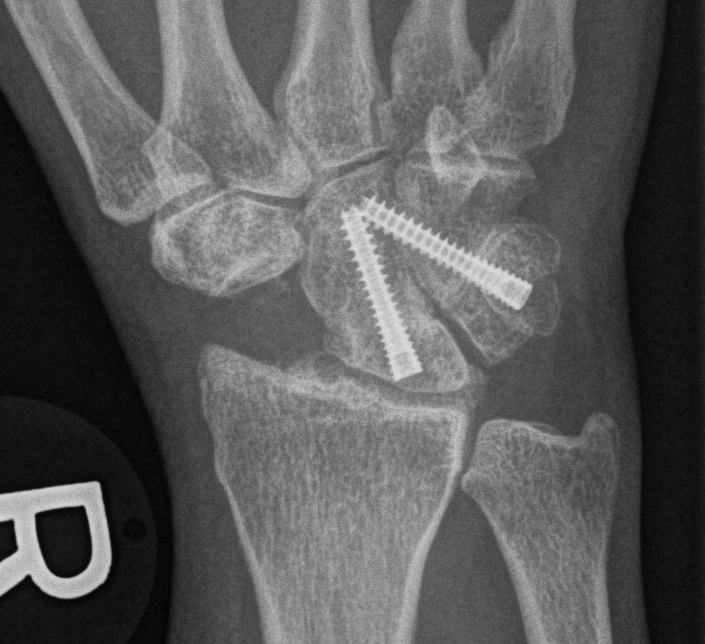

Fixation

- headless compression screws

- dorsal circular plate

- K wires

Scaphoidectomy & Four Corner Fusion

Technique

- resect scaphoid

- denude surfaces of lunate / capitate / hamate / triquetrum

- use good quality BG from distal radius

- must reduce the lunate out of extension or will impinge dorsally